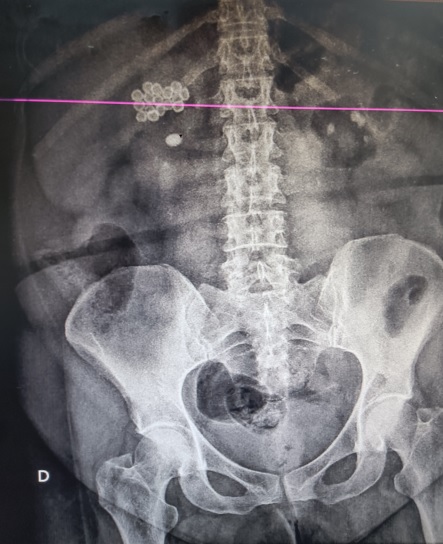

Se solicita radiografía de abdomen para valorar diagnósticos diferenciales y mejor caracterización.

Se realiza ecografía clínica (POCUS) en la que se evidencia vesícula biliar con múltiples cálculos Murphy ecográfico positivo, vía biliar no dilatada. Además en riñón derecho se objetiva imagen cálcica de 1 cm con hidronefrosis grado II. No presenta líquido libre, aorta dentro de parámetros normales.